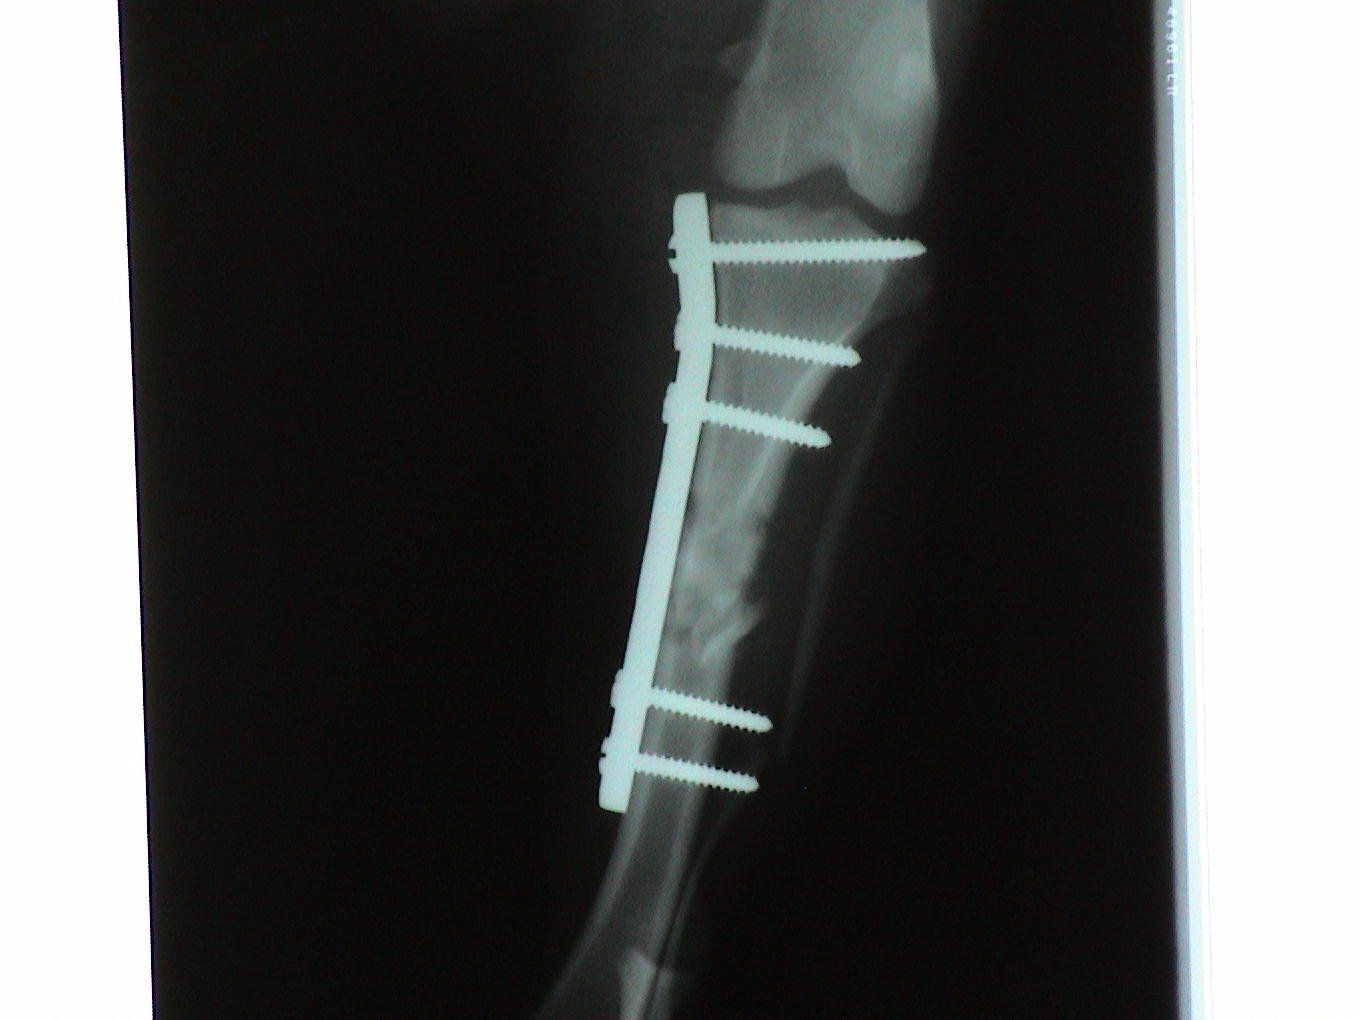

Dogs and cats commonly experience fractures secondary to trauma. The most common cause of the trauma is being hit by a car. Other trauma such as falls from furniture, jumping on unstable surfaces, leaping from a person's arms, etc. can also result in fractures. Below are some x-rays of some of the fractures we have seen at All Pets and their surgical correction using pins, plates, screws, and/or wires.